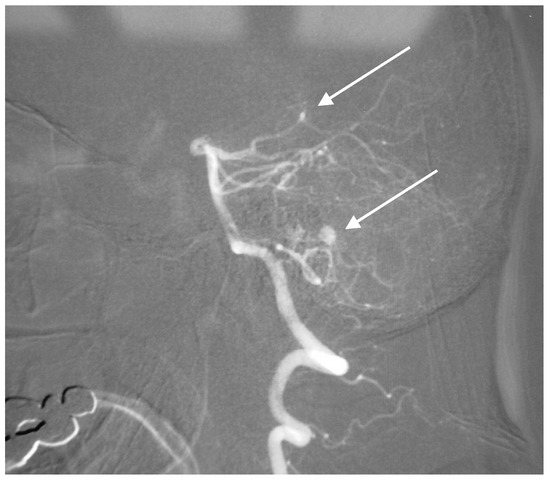

A 50-year-old man presented with a headache. Magnetic resonance imaging (MR) and angiography showed cerebellar AVM and two aneurysms on the right side of the PICA (Figure 6 and Figure 7). The patient underwent an operation, and AVM was successfully resected with both aneurysms clipped. The control angiogram showed good result of the treatment (Figure 8), the postoperative course was without complication, and the patient was discharged.

Figure 6. Anteroposterior (AP) angiogram showing cerebellar AVM (short arrow) and two PICA aneurysms (long arrow).